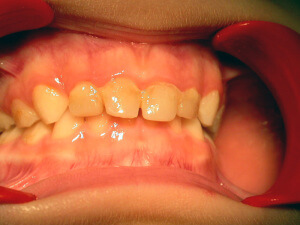

Aesthetic problems

Αισθητικά προβλήματα – εκτός από τα ορθοδοντικά – προκύπτουν και από χρωστικές που επικάθονται στα δόντια. Η χρωστική αυτή πολύ συχνά είναι μαύρη (μελανή χρωστική) και οφείλεται στα λεγόμενα χρωμογόνα μικρόβια. Επίσης, όχι και πολύ σπάνια, υπάρχουν αισθητικά προβλήματα από μη τέλειο σχηματισμό της αδαμαντίνης, πριν ακόμη ανατείλουν τα δόντια (Υπενασβεστίωση τομέων-γομφίων, ατελής αδαμαντινογένεση κλπ).